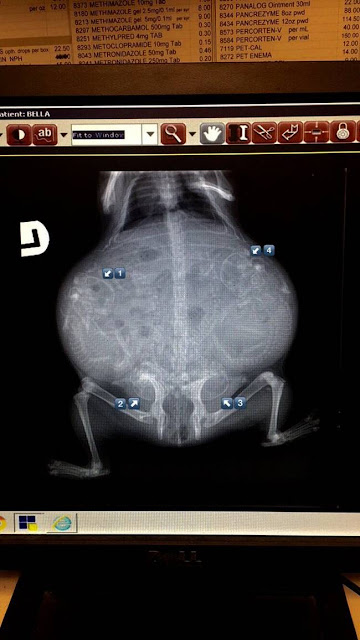

Gata